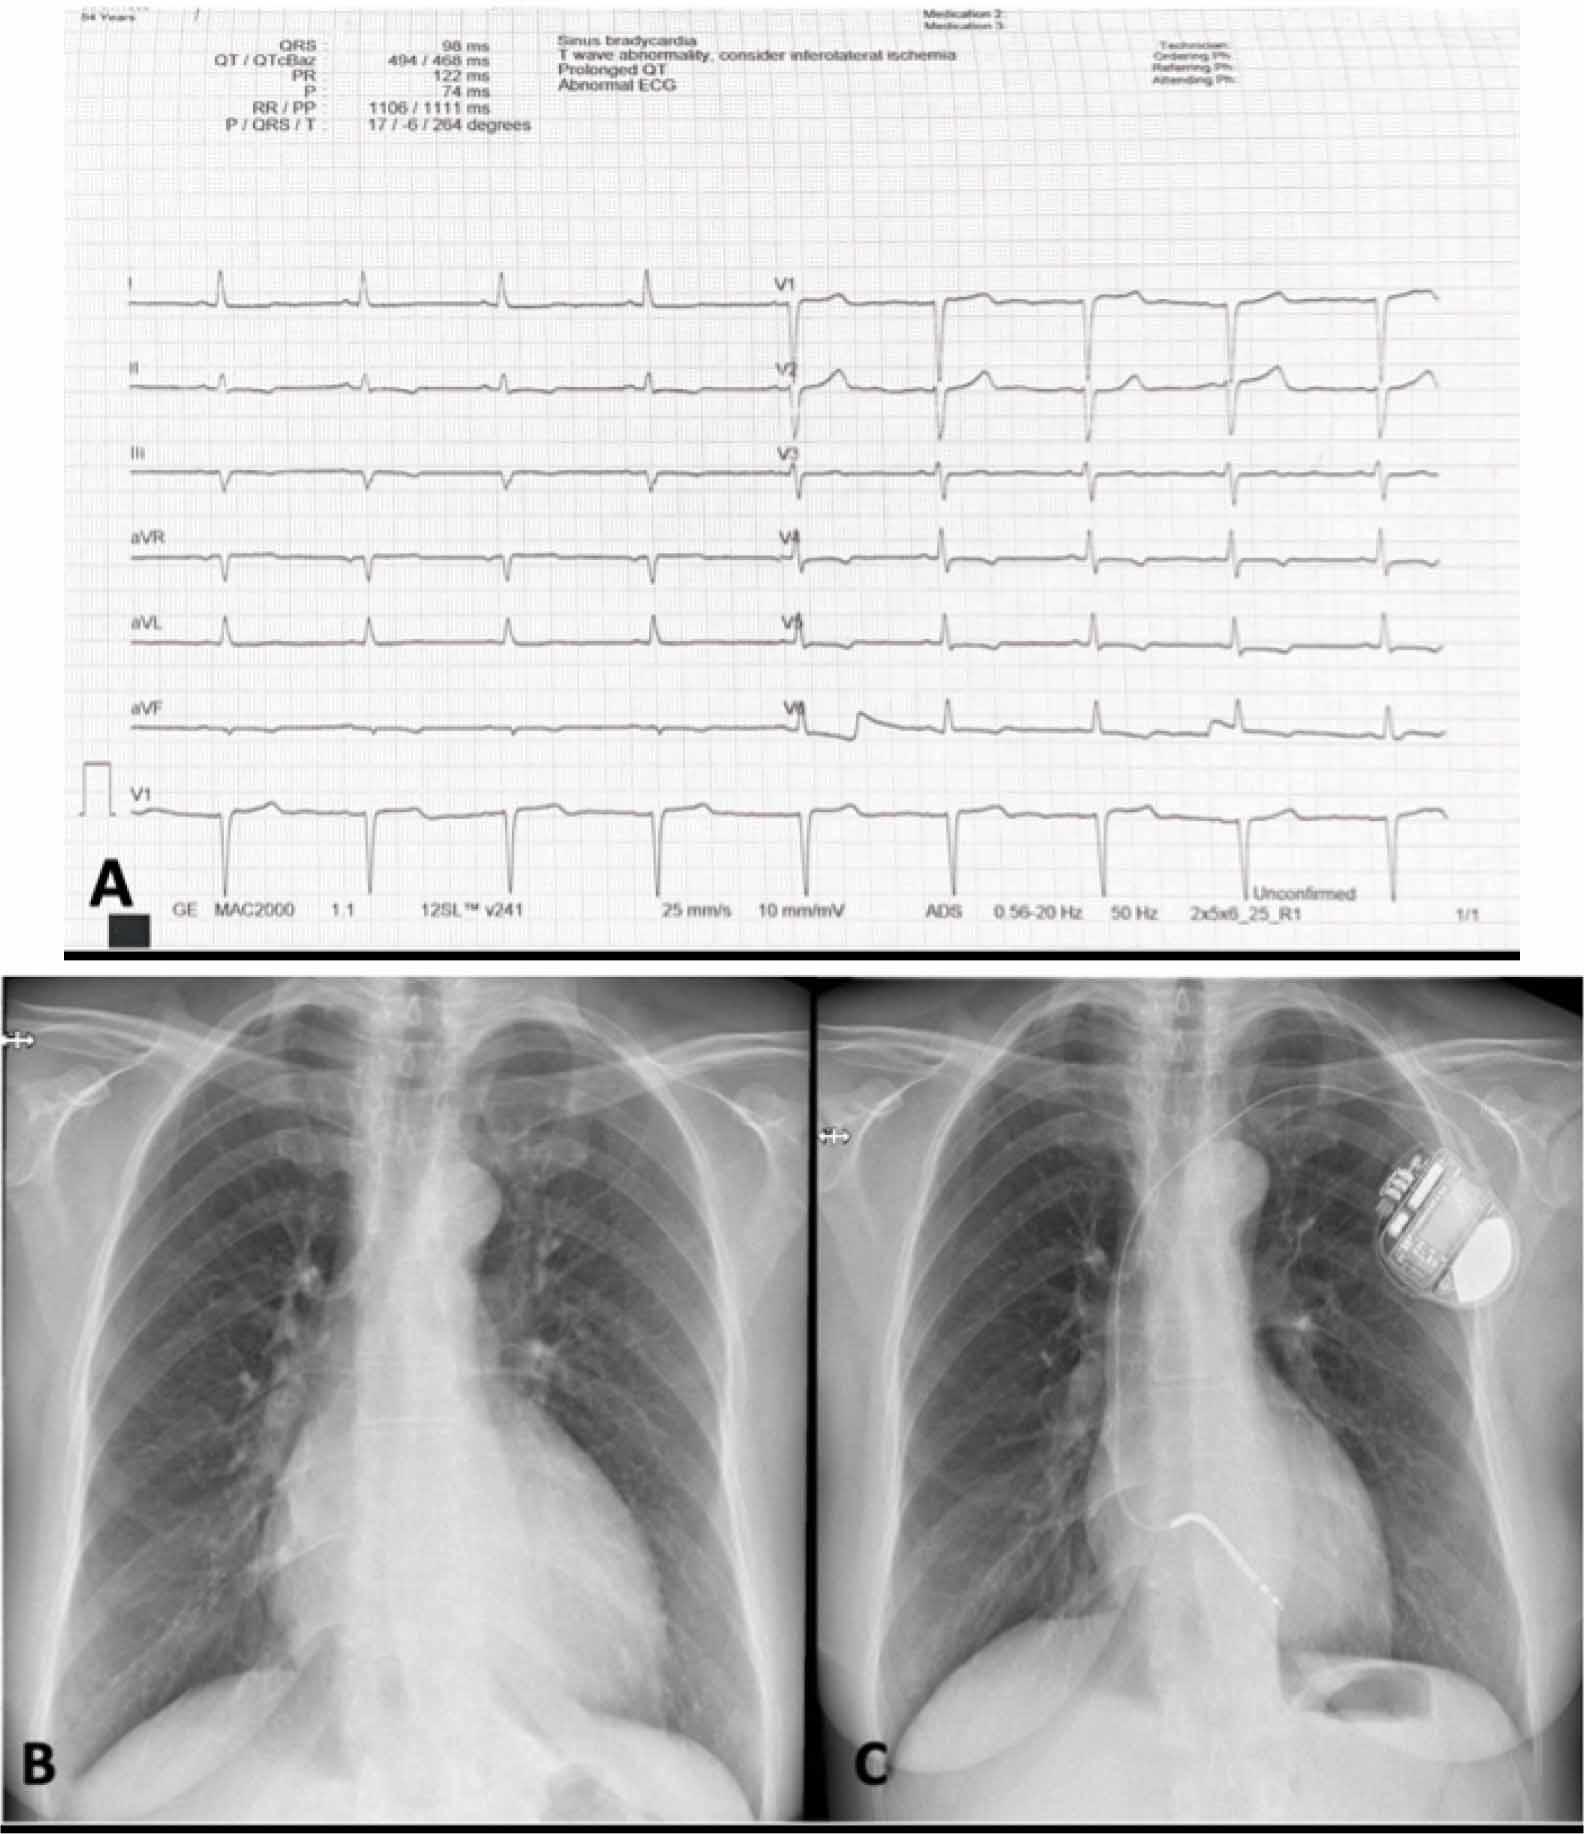

The cardiac physical examination highlighted a grade 2/6 systolic murmur, best heard at the apex, mild leg swelling, a low blood pressure of 90/60 mmHg, and a heart rate of 64 bpm, with rhythmic heart sounds. Biologically, she presented elevated NTproBNP of 5453pg/ml, normal level of troponin, and elevated serum creatinine level of 1,6 mg/dl, corresponding to a glomerular filtration rate of 35 ml/min/1.73 m2. The electrocardiography noted sinus rhythm, with normal QRS axis, narrow QRS (95ms), T-wave inversion in leads V4-V6, DII, DIII, and aVF (Figure 1A), with a corrected QT interval of 470ms; without any significant arrhythmia during 24-hour Holter monitoring.

Electrocardiogram findings showing T wave inversion in inferior and lateral leads with a QTc of 470 ms (A), Admission chest X-ray reflecting prominent convexity of the lower right and left arches suggestive for left atria, respectively left ventricle enlargement, and marked interstitial pulmonary pattern (B), After 3 months, the post-implant radiography of the patient with unicameral implantable cardioverter-defibrillator (C).

We initiated treatment with intravenous loop diuretics administered intermittently for three days until euvolemia was achieved. Subsequently, she was transitioned to an oral diuretic regimen (furosemide 40 mg once daily). Additionally, she was started on optimal heart failure therapy for reduced ejection fraction at the maximum tolerated doses, including a beta-blocker (bisoprolol 5 mg once daily) and a mineralocorticoid antagonist (MRA - spironolactone 25 mg once daily). Considering the presence of a bilateral ureterostomy, a bacteriologic examination was performed, revealing a positive result for Enterococcus faecalis. Following antibiotic treatment and confirmation of a sterile urine culture, a sodium-glucose cotransporter-2 (SGLT2) inhibitor (dapagliflozin 10 mg once daily) was introduced. Despite ESC guideline recommendations for sacubitril/valsartan as first-line therapy, symptomatic hypotension (80 mmHg) occurred even at the lowest dose of ramipril (2.5 mg once daily), which precluded ARNI initiation. Additionally, because she remained with a reduced LVEF of less than 35% after 3 months of maximally tolerated optimal therapy, a unicameral implantable cardioverter-defibrillator (ICD) was considered for primary prevention of SCD (Figure 1C).